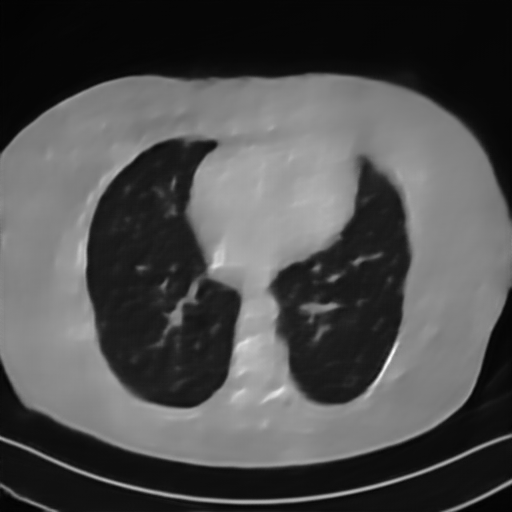

We further increase the noise level contained in the raw data to 10% white Gaussian noises and list the quantitative results in Table IV. It can be observed that the reconstruction performance of the TV model is poor in the case of high-level noises with PSNR dropping by 4 to 5 dB compared to the previous experiments. On the other hand, the performance of the learning-based methods is less sensitive to noises. The SIPID method relying on the sinogram interpolation works better than FBP-Unet. And the deep unrolling methods (i.e., PD-net, IFSR-net, SFSR-net) outperform the traditional iterative algorithm when the scanning range is limited and data is corrupted by noises. Similar to the previous experiments, compared with other deep learning algorithms, our LRIP-nets give the reconstruction results with higher PSNR and SSIM. Moreover, the low-resolution image obtained by the projection data down-sampled with rate 1/8 always gives the best reconstruction results with more than 2 dB PSNR and 0.05 SSIM increments compared to the PD-net. Fig. 6 illustrates the reconstructed images from different methodologies with scanning angular range of and 10% Gaussian noises. It can be seen that the both TV model and the FBP-Unet suffers from significant artifacts, which present distortions in the angular range of the missing scan. Other learning-based methods provides better visual qualities than FBP-Unet, and our LRIP-net1/8 still gives the best reconstruction result with correct boundaries and fine structures.